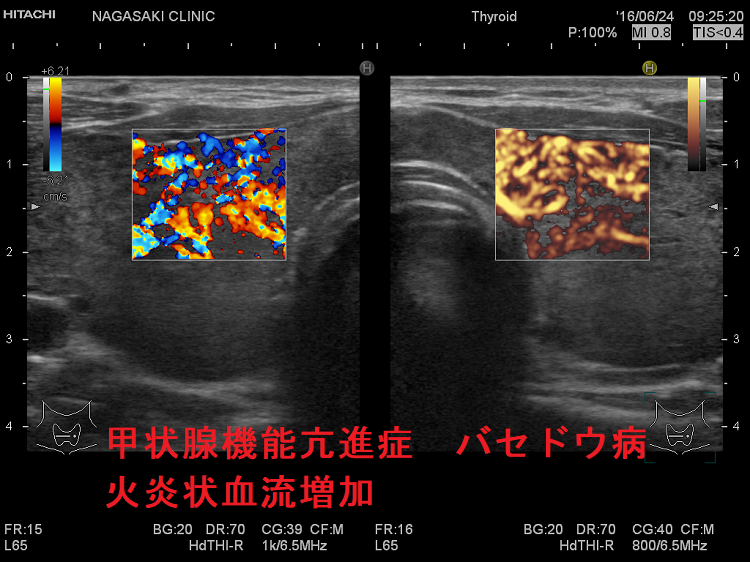

甲状腺機能亢進症バセドウ病 火炎状血流増加

甲状腺機能亢進症/バセドウ病の火炎状血流増加;著明な血管増殖のため甲状腺内の血流が増加します。

しかし、無痛性甲状腺炎でも、甲状腺機能低下症でも血流増加するため、これだけでは鑑別できません。

甲状腺機能亢進症 バセドウ病 火炎状血流増加

甲状腺機能亢進症/バセドウ病の火炎状血流増加